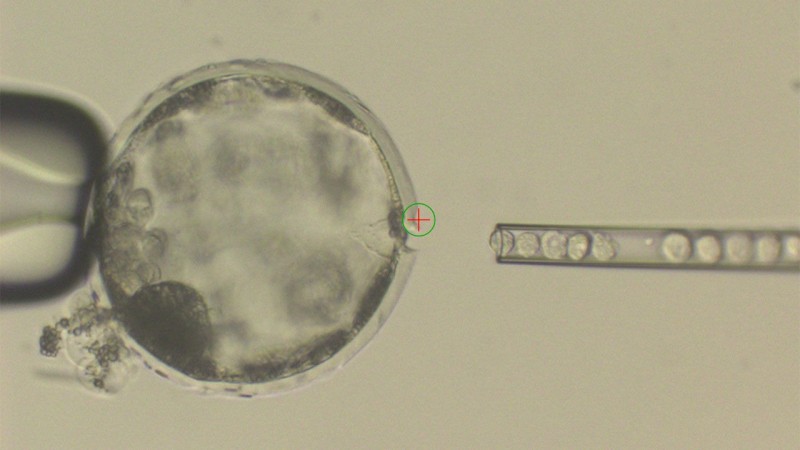

Энэхүү зорилгодоо хүрэхийн тулд хүнээс өөр төрөл зүйлийн амьтны ДНХ-г ашиглан тухайлсан амьтны эд, эрхтэн хөгжиж чадах эсэхийг харахын тулд хулганы үр хөврөл рүү хархны үүдэл эсийг оруулж анхны харх-хулганы эрлийзийг гарган авчээ Энэхүү аргаа гахайд ашиглаж хүн-гахайн эрлийз үр хөврөлийг бий болгож түүнийг эм гахайнд шилжүүлэн суулгасан байна. Ингээд эрдэмтэд өсөлт хэвийн явагдаж байгаа эсэхийг шалгахын тулд 3-4 долоо хоногийн туршид байнгын хяналтанд байлгах явцад тээгч эсүүд зөвхөн булчингийн бүтцэд муу нөлөө үзүүлж буйг ажигласан байна. Уг судалгааны ажлын үр дүнгээ “The Cell” сэтгүүлд хэвлүүлсэн нь нилээд найдвар төрүүлж, эрдэмтдийн анхаарлыг татаад байна. Тухайлбал: Эдинбургийн Их сургуулийн, амьтны биотехнологийн профессор, Рослин Институтын орлогч захирал, Брусс Вайтлав (Bruce Whitelaw): “Энэ өгүүлэл үнэхээр сэтгэл догдлом, гахайны үр хөврөлд хүний эсийг нэвтрүүлснээр хүн-гахайны эрлийзийг бараг л гаргаж ирснээр үл барам шинжлэх ухааны үр дүнтэй нийтлэл болж чадсан. Энэ нь үр хөврөлийн эсийн хөгжил, механизмыг ойлгох боломж олгож байгаагаас гадна хүний эсийг ашиглаж чадвал онцгой чимерануудыг гарган, хүний эд эрхтнийг ургуулан шилжүүлэх боломжийг бүрдүүлж байна. Мөн чимераг бүтээснээр эрдэмтэд ургийн өсөлт хөгжил, өвчин дарангуйлах системийг ойлгож авахаас гадна шинэ эмийг туршиж биотехнологийн шинэ бүтээгдэхүүн гарган авах боломжтой юм” гэжээ.